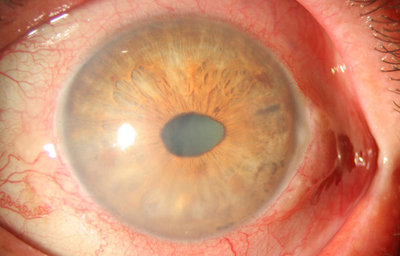

Aniridia completa, catarata y distrofia corneal de la aniridia

Archivo Dr. Francisco Barraquer

Caso de paciente con Coloboma en un ojo y Aniridia en el contralateral

OD

Archivo Fotográfico Dr. Francisco Barraquer

OI

Archivo Dr. Francisco Barraquer